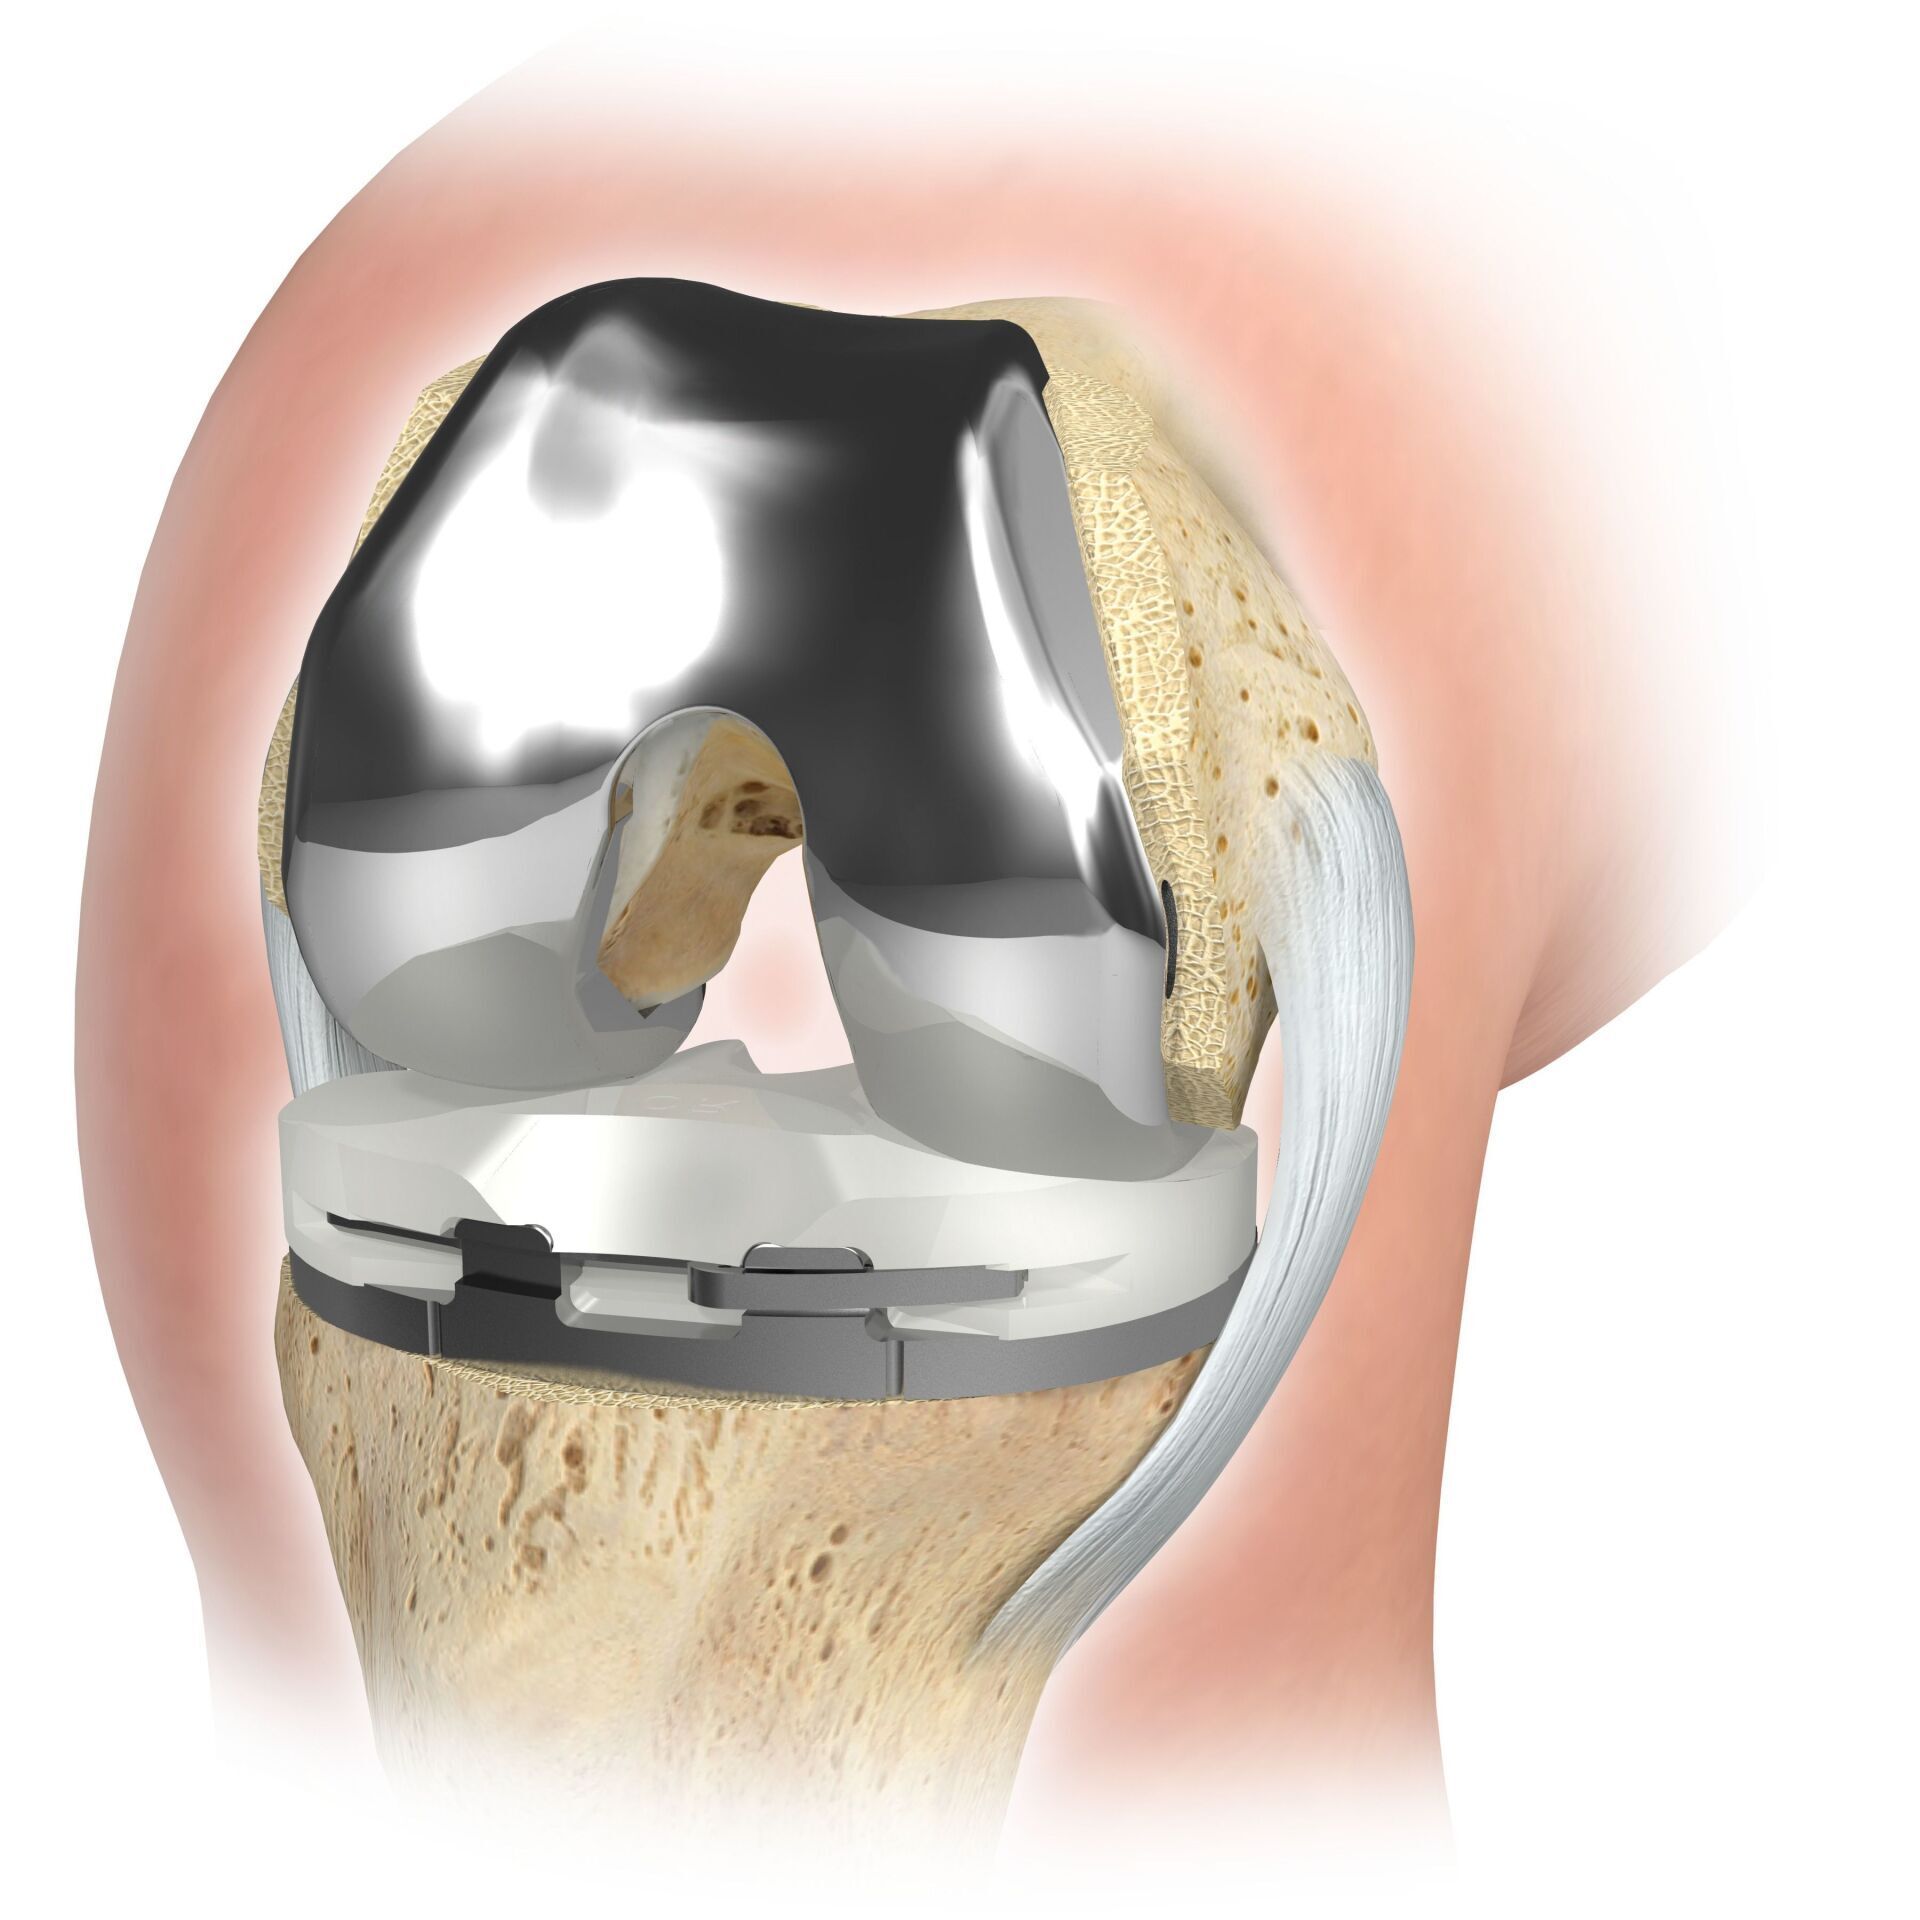

Partial joint replacement the knee joint is possible in all areas of the joint, but is most often carried out on the inside of the knee joint and is often colloquially referred to as a sled prosthesis . Similar to the full denture, the defective cartilage is replaced with a new surface and a plastic inlay is inserted in between. For a partial prosthesis, all ligament structures, especially the cruciate ligaments, must be largely intact.

TKA (ARTIFICIAL KNEE JOINT)

The artificial knee joint replaces the cartilage surface that has been destroyed by osteoarthritis.

The underlying bone on the femur and tibial head remains intact. Some compare a modern artificial knee joint to a crowning of a tooth; the exact term is the so-called

bicondylar resurfacing. Between the new surfaces on the upper and lower leg is the so-called inlay made of a specially hardened white plastic, which can be seen in the X-ray image as the distance between the metal parts.